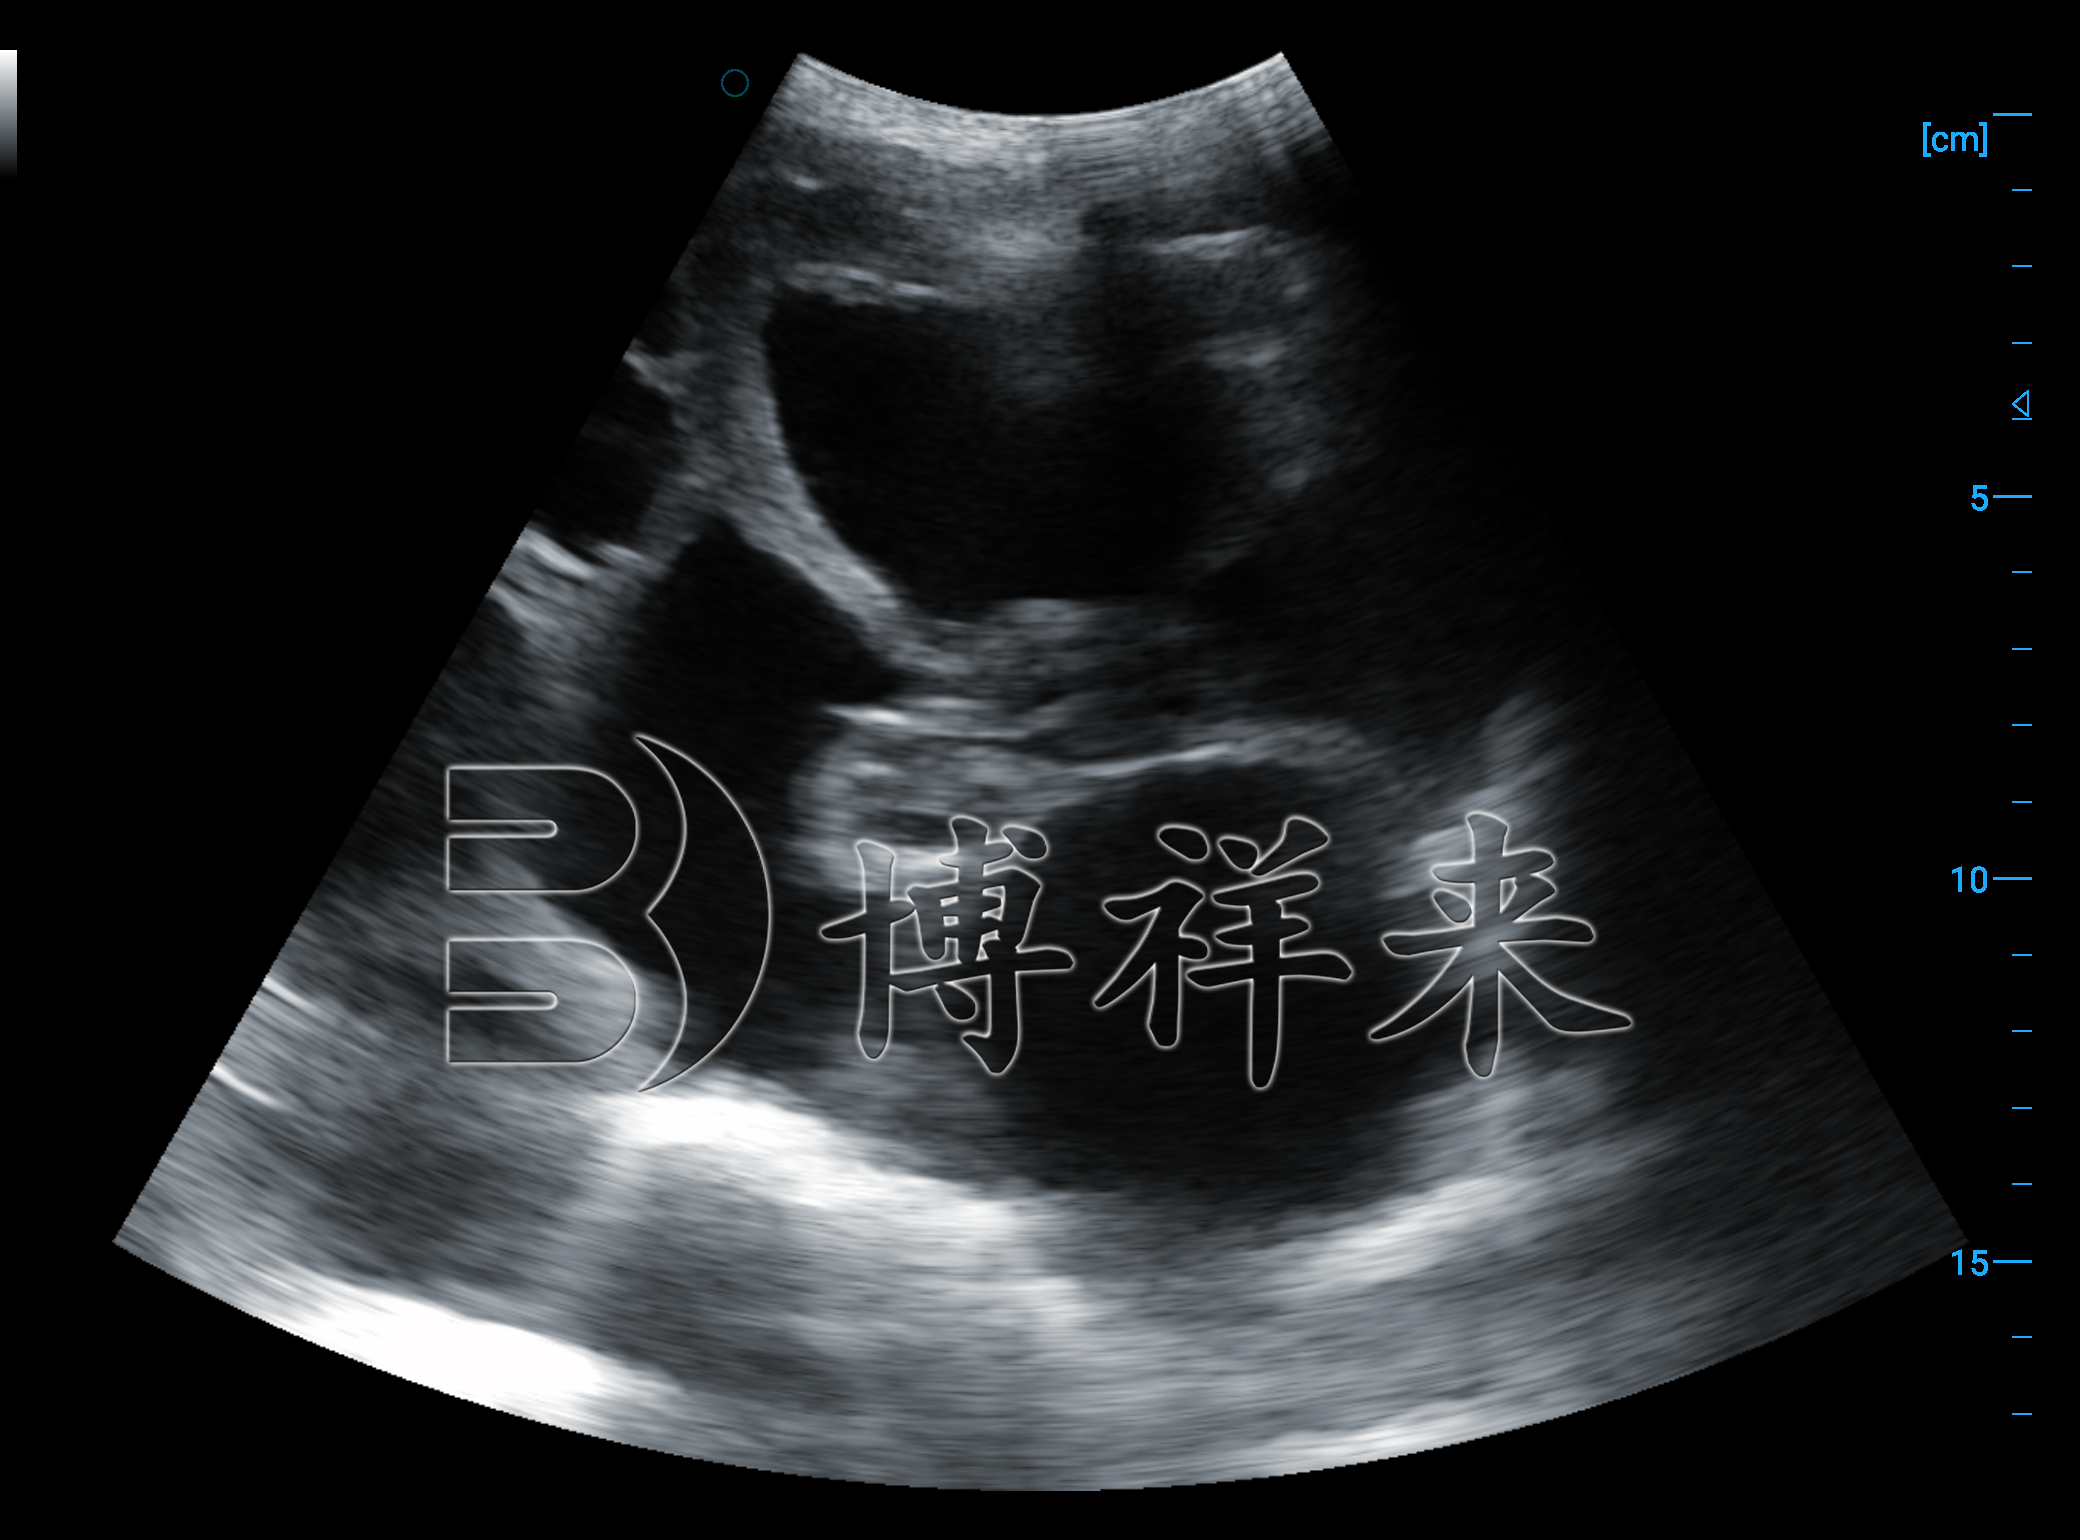

好的猪用B超机能明显看清以下结构:

胎囊

胎骨

卵泡

胎头轮廓

羊膜内回声变化

清晰度越高,误判率越低,尤其在“早孕检测”和“卵泡监测”中差异更为明显。